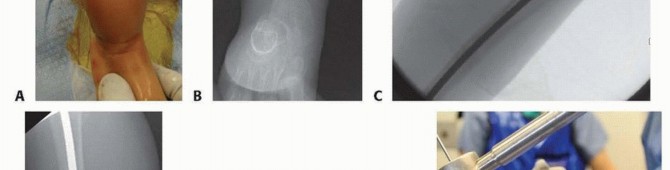

Cutting and Insertion of the Female Nail

## To measure the length of the female rod intraoperatively, it is placed with the threaded portion just at the top of the ossified greater trochanter with C-arm verification using a metal marking device distally approximately 1 cm above the physis (TECH FIG 3A).

## The female nail is covered with K-Y Jelly (Johnson & Johnson, New Brunswick, NJ), then cut with a diamond-tip burr and cooled with sterile saline.

## The cannulated portion must be checked to ensure that no metal will impinge on the male nail to prevent it from lengthening and that any metal shards are rinsed off (TECH FIG 3B,C).

## A circular saw and rod holder are also available from the manufacturer to cut the female rod (TECH FIG

3D).

## The male nail driver is then removed, and the female nail is placed over the male nail.

## The female nail is then screwed into the greater trochanter with the T-handle screwdriver until just a few threads are engaging the bony portion of the proximal femur just distal to the greater trochanter (TECH FIG 3E).

## The female nail is checked distally to be sure there is some space between its distal end and the guide wings of the male nail to ensure that the male nail is not driven distally into the joint either acutely or with impaction of the osteotomy with weight bearing (TECH FIG 3F,G).

## If the female nail is too shallow proximally, it will back out, but if it is too deep, it is more likely to become overgrown and ultimately reside in the femoral canal.

## The male nail is then cut in situ with the male nail cutter (TECH FIG 3H).

## Cutting the male nail approximately 1 cm above the top of the female nail rarely causes persistent symptoms and allows for more growth.

## The probe is used to ensure that the cut male nail is smooth and not bent, which would prevent telescoping.

TECH FIG 3 • A. Measuring the female nail length intraoperative with fluoroscopy. B,C. Cutting the rod with diamond burr. D. Manufacturer's female nail holder with cutting wheel and burr to smooth rough internal edges after cutting. (continued)

## TECH FIG 3 • (continued) E. The female threads are shown engaging the bone just distal to the greater trochanter to mitigate overgrowth of the trochanter apophysis but avoid proximal migration of the female nail. F,G. Distal placement of the male nail driver and nail in the center-center position is mandatory. The threads engage the epiphysis of the distal femur with the rounded, smooth portion traversing the physis.

Ideally, the distal end of the female nail is as close as possible to the guide wings of the male nail for strength and growth but leave room for compression at the osteotomy. H. The male nail is cut in situ with the male nail cutter. (D: Courtesy of Pega Medical, Inc., Montreal, Canada.)